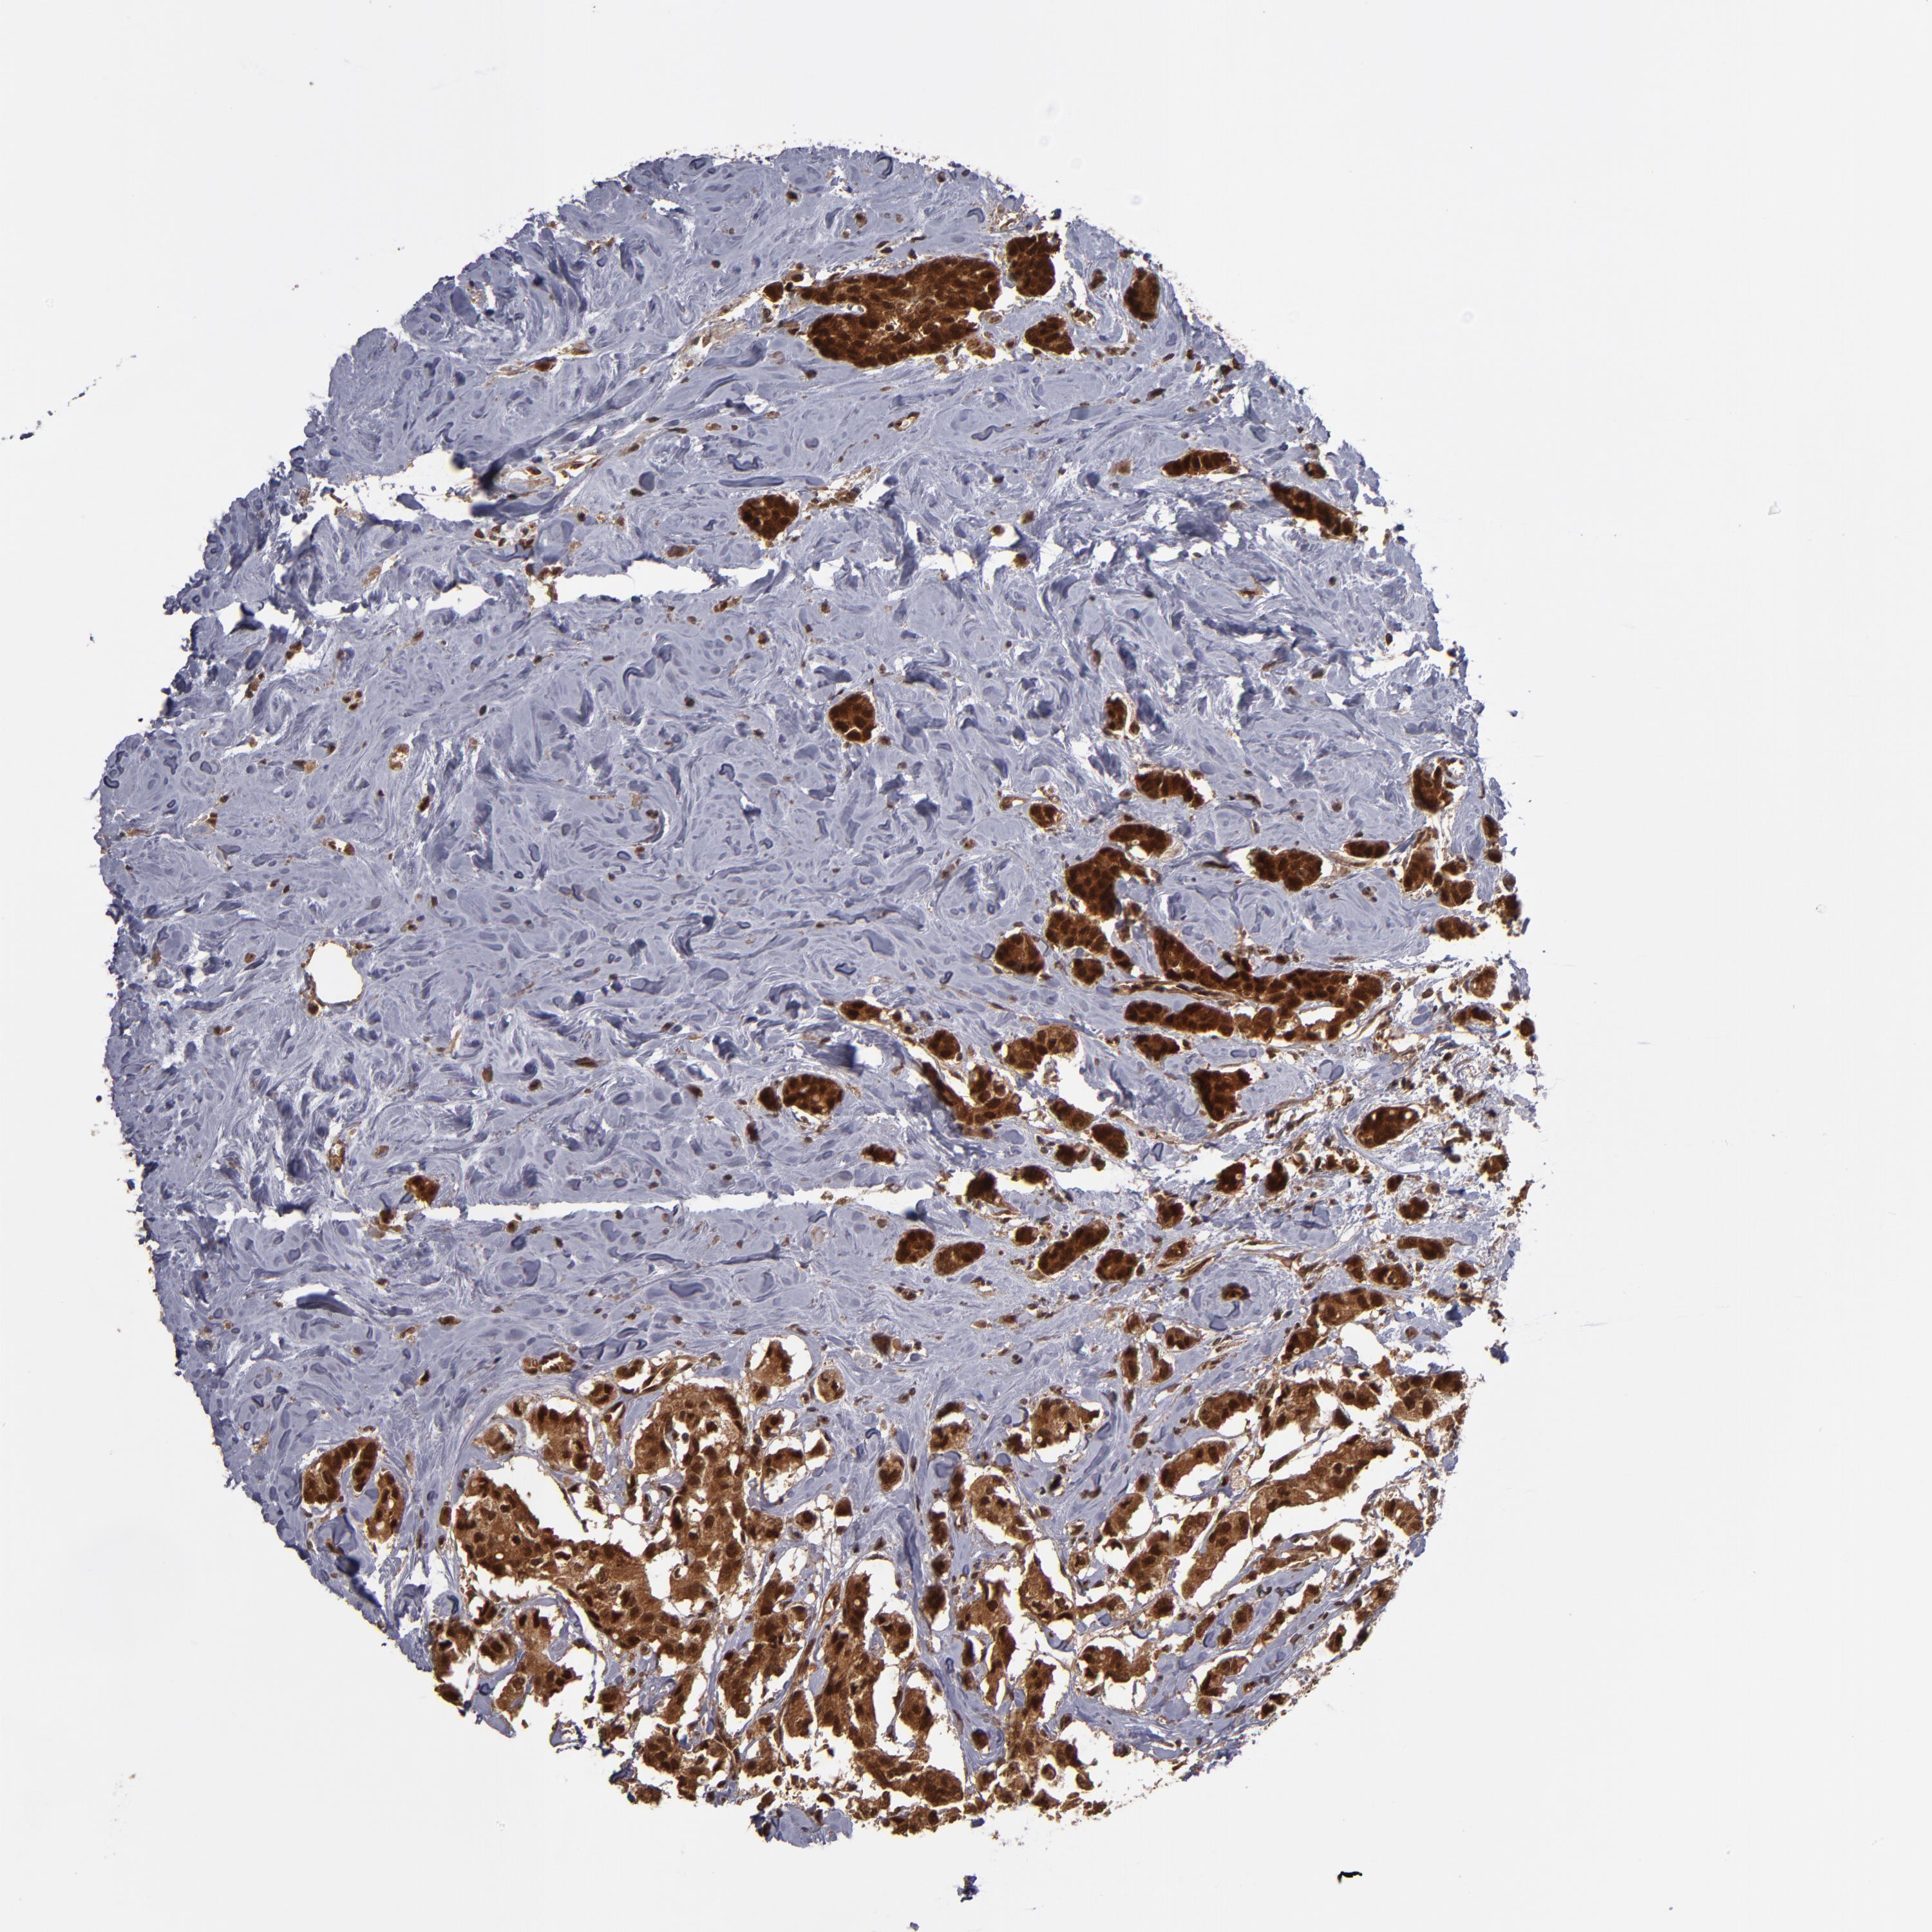

BRCA TCGA BRCA VALIDATION PROTEIN EXPRESSION

ANTIBODIES

AND

VALIDATION